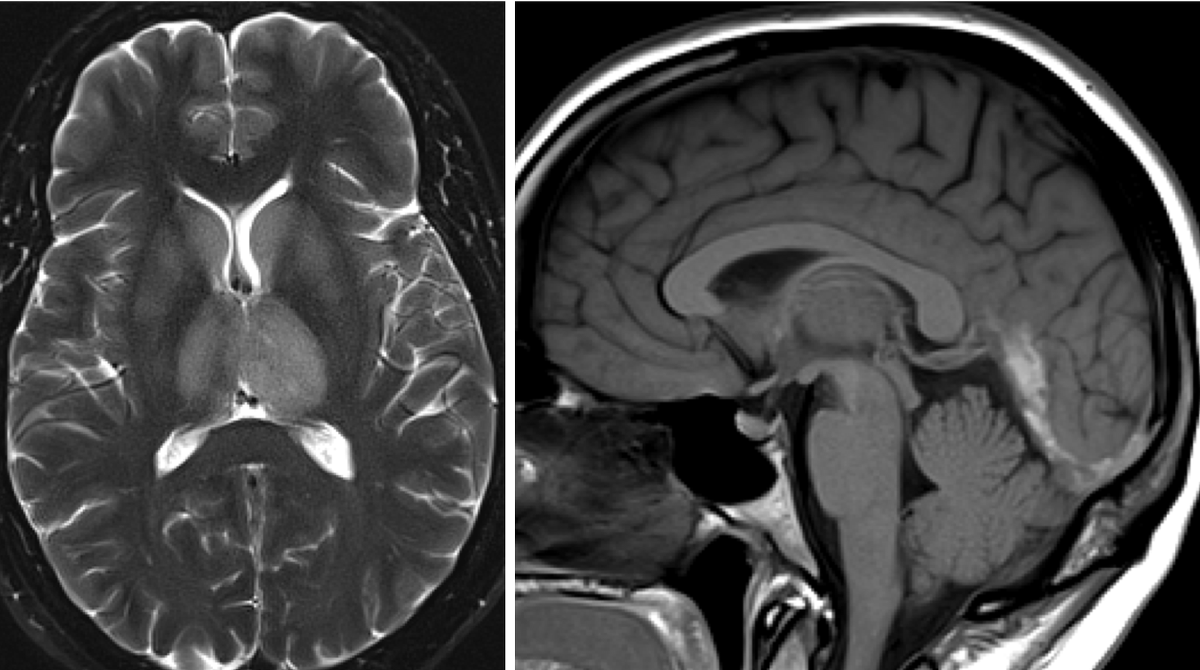

A nice example of the noncontrast brain MRI appearance of a can’t miss diagnosis for on call

#RadRes and#Neurorad fellows. See http://bit.ly/2GW8GGu for answer.#FOAMradpic.twitter.com/J7mifl1qhx